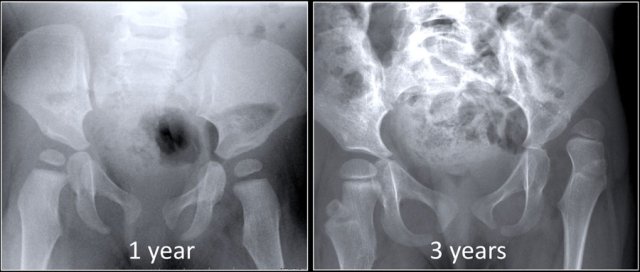

There are children who are born with normal hips who develop dysplasia (figure).

In this case the child had a neuromuscular disorder which caused the hip to become dysplastic and dislocate.

On the other hand there are children who are born with dysplasia of the hip that resolves spontaneously or after relatively simple treatment, e.g. a Pavlik harness (figure).

So we have to realize that DDH is a dynamic disease and it is not always present at birth as suggested by the name congenital hip dysplasia.

Treatment is easier and complications are less likely to occur when DDH is diagnosed early.

In this case at 13 months the only sign of the former dysplasia is the delay of the femoral head to ossify.